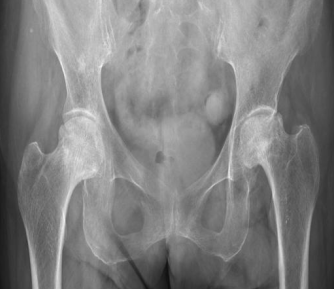

▲患者术前影像学检查

▲正常股骨头形状

▲股骨头坏死的改变